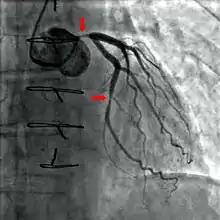

A coronary angiogram (an X-ray with radiocontrast agent in the coronary arteries) that shows the left coronary circulation. The distal left main coronary artery (LMCA) is in the left upper quadrant of the image. Its main branches (also visible) are the left circumflex artery (LCX), which courses top-to-bottom initially and then toward the centre/bottom, and the left anterior descending (LAD) artery, which courses from left-to-right on the image and then down the middle of the image to project underneath the distal LCX. The LAD, as is usual, has two large diagonal branches, which arise at the centre-top of the image and course toward the centre/right of the image.